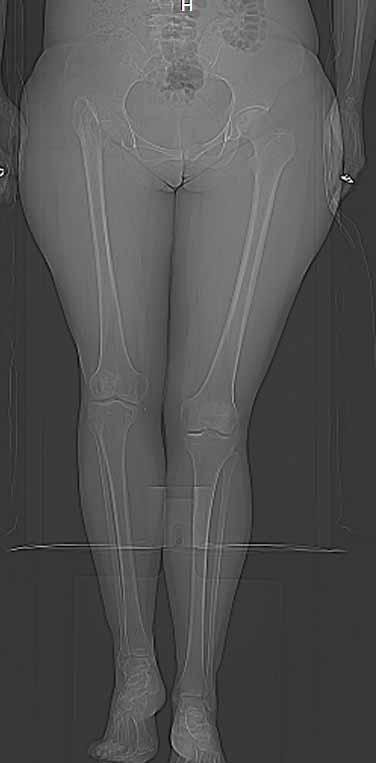

Поскольку основная жалоба на укорочение конечности, то я ей предложил удлинить голень. Величину удлинения обсудили - в пределах 4 см.

Сделал ей КТ.

С удивлением узнала, что перелом в области шейки у неё не сросся, хотя на рентгенограмме тех лет так оно и есть.

Интересна функциональная адаптация - практически полная функция того, что раньше было тазобедренным суставом.